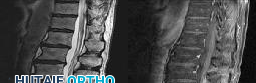

Figures 1 through 3 show sagittal and axial MRIs and a radiograph from a

77-year-old woman with leg pain when standing and walking of 1 year duration. The pain improves when she leans forward. She has been in physical therapy, taken oral analgesics, and had epidural injections with minimal relief. What is the best next step?

4. Microdiskectomy Discussion: B

The patient has lumbar stenosis of L2-3 and L3-4. She has no spondylolisthesis or instability. For her condition, spinal fusion plays a minimal role. She has no evidence of instability, and her condition can be addressed through laminectomy only. No role exists for microdiskectomy, because her disease results from a combination of ligamentum flavum hypertrophy and facet hypertrophy.